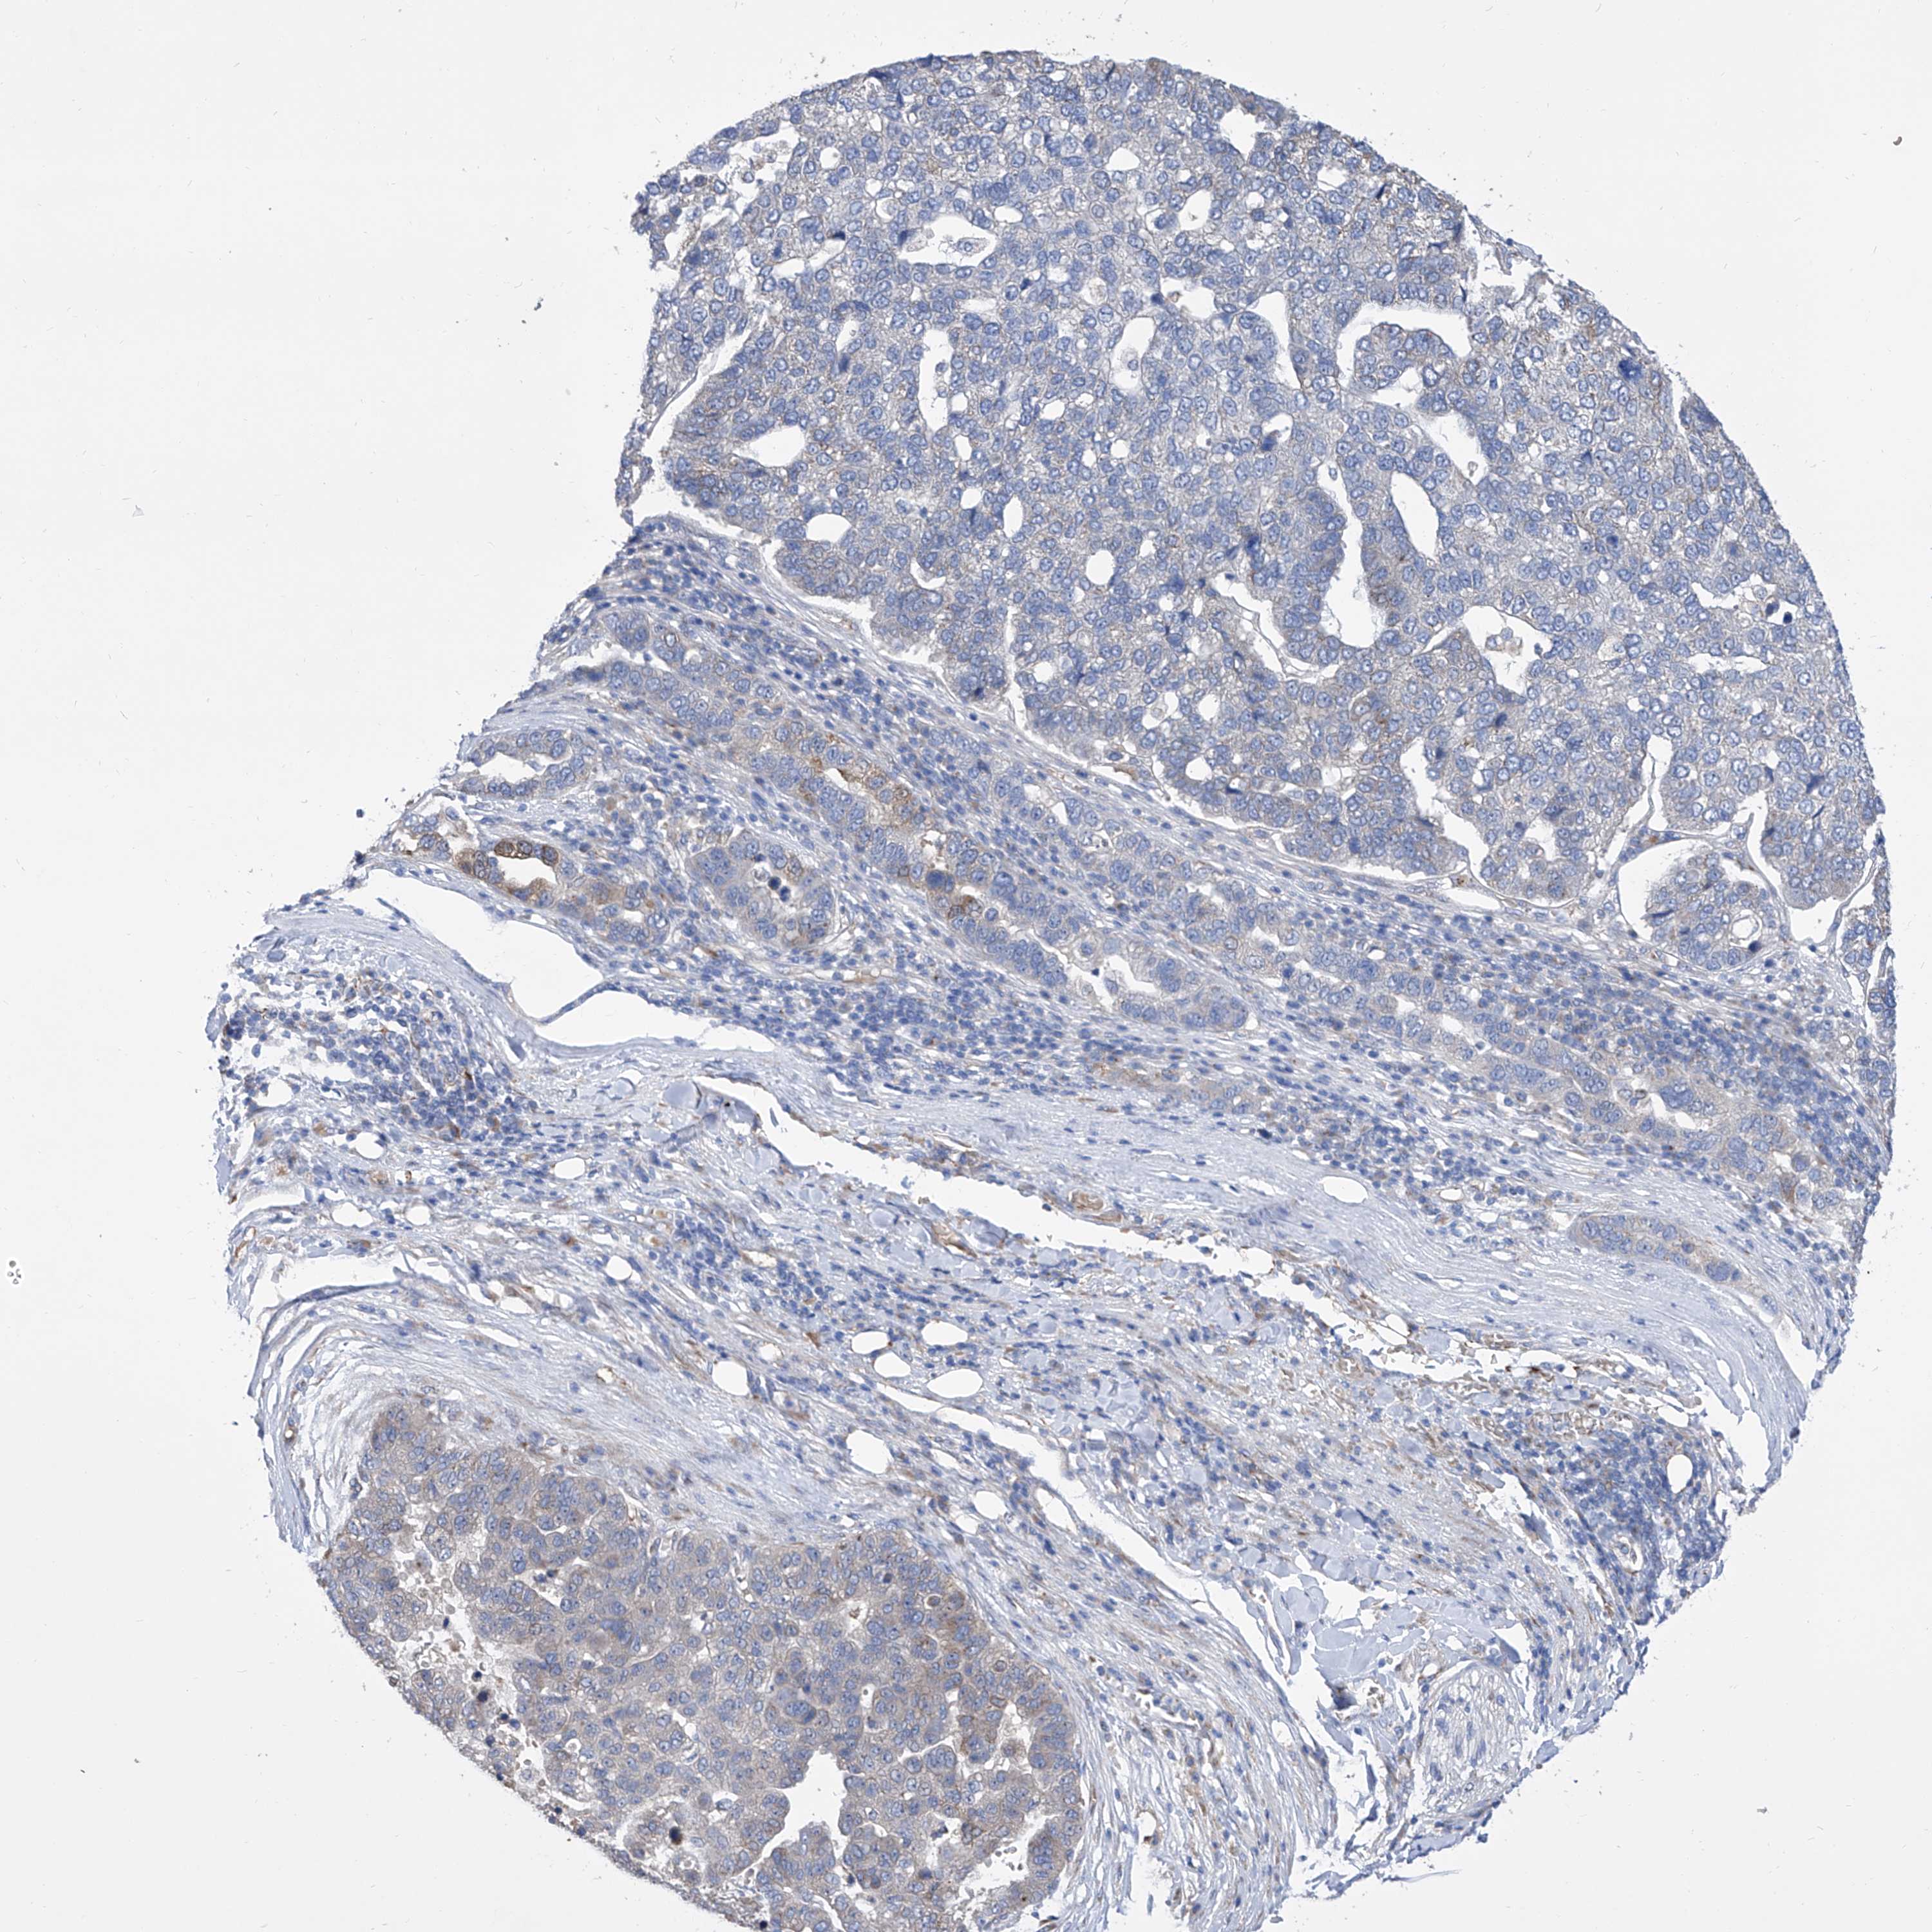

PANCREATIC CANCER - Protein expressioni

A mouse-over function shows sample information and annotation data. Click on an image to view it in a full screen mode. Samples can be filtered based on level of antibody staining by selecting one or several of the following categories: high, medium, low and not detected. The assay and annotation is described here.

Note that samples used for immunohistochemistry by the Human Protein Atlas do not correspond to samples in the TCGA dataset.

Antibody stainingi

Antibody staining in the annotated cell types in the current human tissue is reported as not detected, low, medium, or high, based on conventional immunohistochemistry profiling in selected tissues. This score is based on the combination of the staining intensity and fraction of stained cells.

Each image is clickable and will lead to virtual microscopy that enables deeper exploration of all samples and also displays staining intensity scores, fraction scores and subcellular localization as well as patient and tissue information for each sample.

Antibody HPA030164

Antibody HPA030165

Antibody HPA030166

Adenocarcinoma, NOS